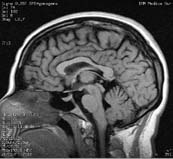

Magnetic Resonance Imaging (MRI) and functional Magnetic Resonance Imaging (fMRI) are two non-invasive imaging techniques that rely on data measured around a part of a subject’s body (e.g. the head) to acquire information about what’s going on inside the body part (e.g. the brain). The data are processed using a mathematical technique called Filtered Backprojection, which is a computationally efficient and stable way of computing the Inverse Radon transform. The MRI machine shown above is made by GE Medical Systems. An example of the kind of data that can be acquired via this technique is the image of a patient’s brain shown below.

Image of patient’s brain acquired via ‘Filtered Backprojection’ technique. (Image courtesy of Prof. Christof Koch. Used with permission.)